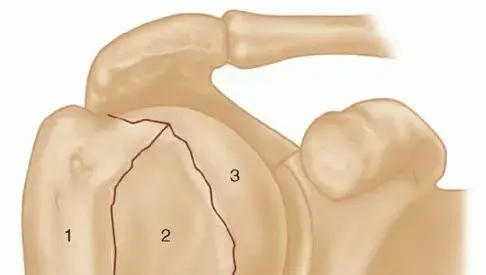

إصابة الثالوث الرهيب (Terrible Triad Injury):

هي إصابة معقدة في المرفق تتضمن ثلاثة مكونات رئيسية:

1.

خلع المرفق:

غالبًا ما يكون خلفيًا جانبيًا.

2.

كسر رأس الكعبرة.

3.

كسر الناتئ الإكليلي.

هذه الإصابة شديدة عدم الاستقرار وتتطلب تدخلًا جراحيًا غالبًا.

الشكل 2:

إعادة بناء ثلاثية الأبعاد بالتصوير المقطعي المحوسب للمرفق الأيمن، تظهر إصابة الثالوث الرهيب المعقدة. يظهر كسر مفتت في رأس الكعبرة (Mason-Morrey Type III)، إلى جانب كسر كبير في الناتئ الإكليلي (O'Driscoll Type IIB). كما يظهر بوضوح خلع الزند الخلفي الجانبي بالنسبة للعضد.